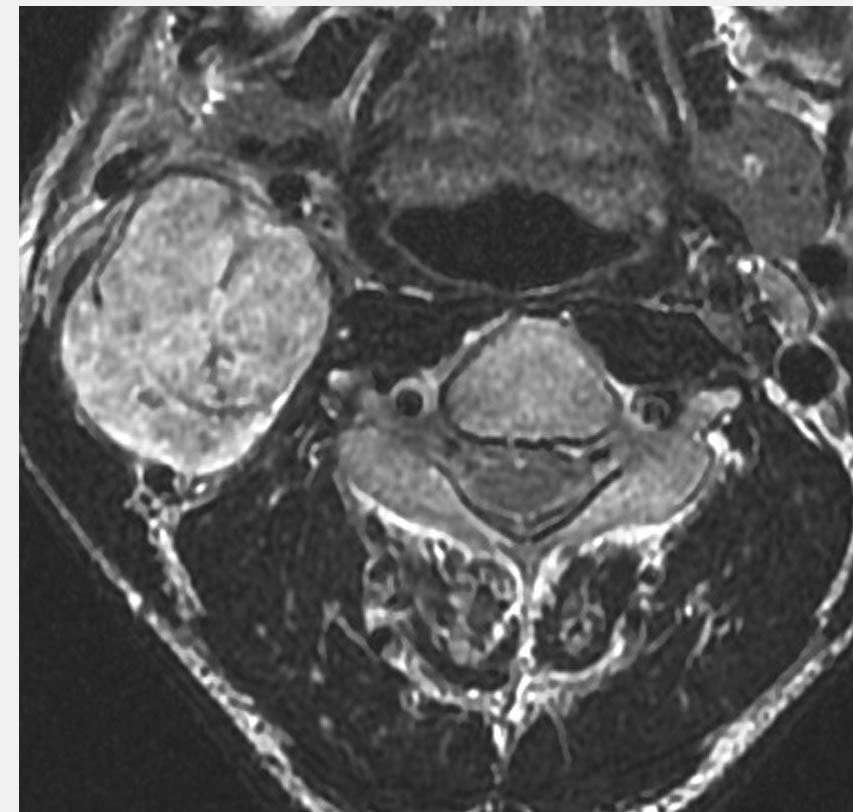

40歳の時に右頸部が腫れているのに気づいて発見され,耳鼻科で生検術され経過をみたものです。7年間の経過観察でかなり増大しました。症状は全くありませんでした。まだ腫瘍増大が止まらないので摘出することにしました。術前は舌咽神経鞘腫と診断することはできません。

手術中に中枢端で舌咽神経本幹に連続性がありここを切断して全摘出しました。それで舌咽神経鞘腫と確定診断ができています。

術後には無症状,他覚的な神経脱落症状はありませんでした。長い間かかって増大したので迷走神経などで代償機能が働いているのだと推定されます。

舌咽神経の末梢枝は,carotid sinusからの感覚神経を含むので,内頸動脈と外頸動脈の間に入り込むように増大することがあります。